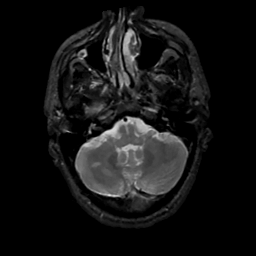

MR Study #1, February 10, 1991 -- Slice #10

[Home][Help][Clinical][Tour 1][Tour 2] Slice 10